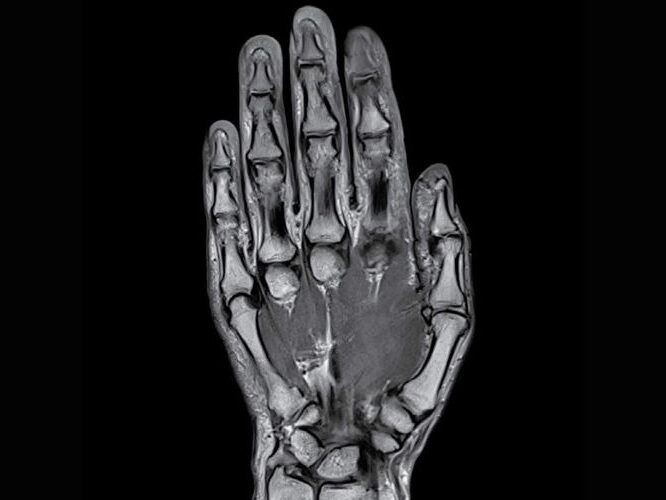

Orthopedic surgery diagnostic imaging with advanced 3T MRI for precise evaluation of bone, joint, and soft tissue conditions and injuries.